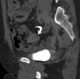

Appendiceal mucocele